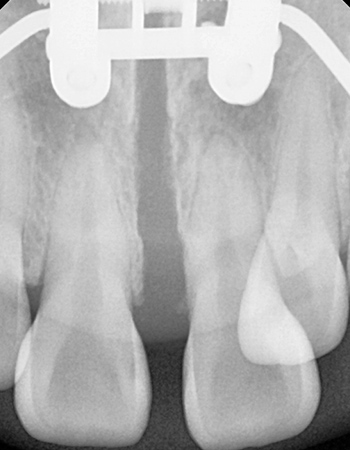

확장 전

확장 후